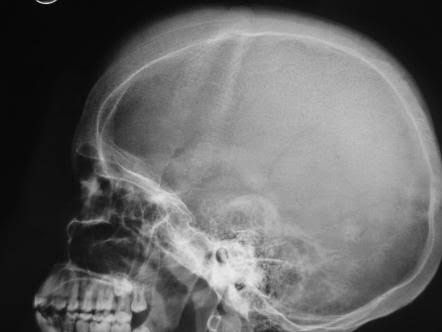

'Hair-on-end' sign is seen in the diploic spaces on the skull radiographs appearing like long, thin vertical striations that resemble hairs standing on ends.. Hair-on-end appearance of the skull is a characteristic feature of chronic hemolysis usually seen in patients with thalassemia and sickle cell anemia.